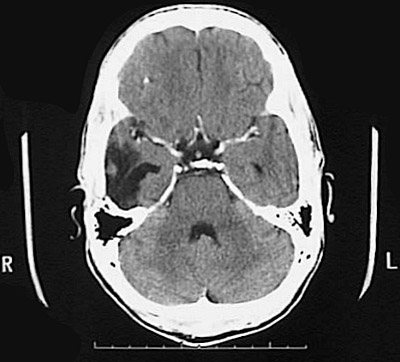

Click on the area of hemorrhage in the CT scan above:

This axial CT scan demonstrates a large area of hemorrhage in the right temporal lobe as a consequence of a ruptured vascular malformation.